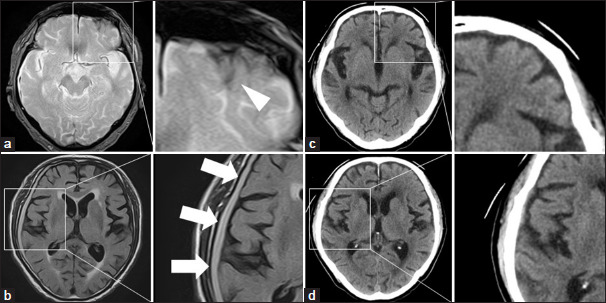

Case description: An 85-year-old male with a 30-year history of insulin-treated type 2 diabetes presented with raccoon sign one morning, without additional symptoms. A comprehensive physical examination, including a detailed head assessment, revealed no abnormalities. However, computed tomography (CT) imaging identified a minor subarachnoid hemorrhage, and high-resolution CT imaging (1-mm bone slice thickness) detected a thin orbital roof fracture, confirming a traumatic contrecoup injury. This finding rendered the differential diagnosis for nontraumatic causes irrelevant. The patient's longstanding diabetes was considered a relevant factor in the development of the raccoon sign.